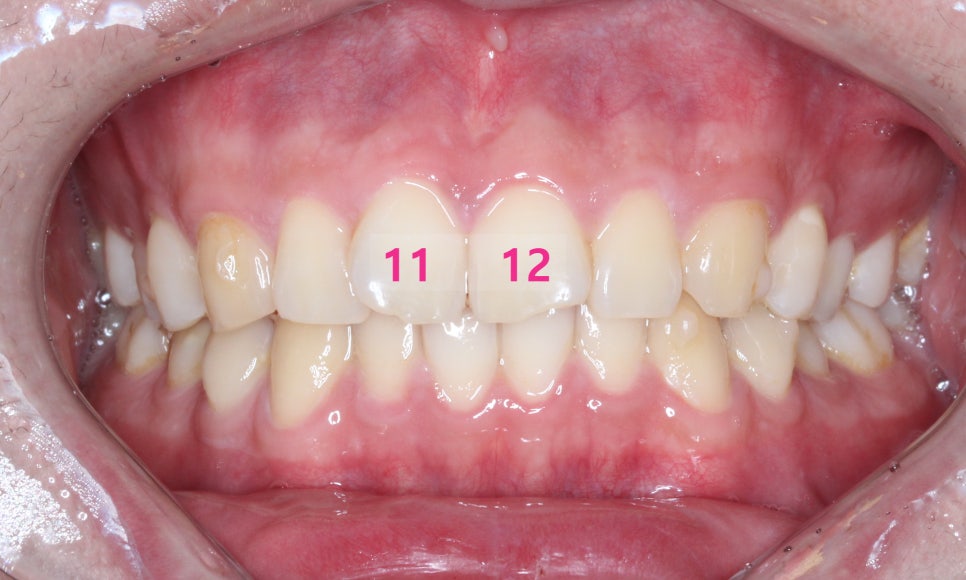

교정 전 사진을 보시면

앞니의 모양

특히 11, 12번 치아의 형태가

V자 모양으로 대칭적이게

틀어져 있는 모습입니다.

문제였던 11번, 12번 치아 역시

V자 형태가 아닌 부드러운 곡선을

띠게 되었습니다!